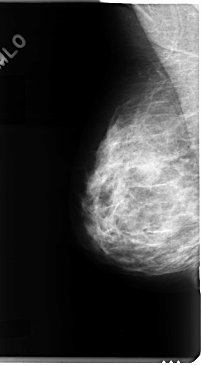

C_0091_1.RIGHT_MLO

C_0091_1.LEFT_MLO

LEFT_MLO LINES 4712 PIXELS_PER_LINE 2544 BITS_PER_PIXEL 12 RESOLUTION 50 NON_OVERLAY

RIGHT_MLO LINES 4744 PIXELS_PER_LINE 2624 BITS_PER_PIXEL 12 RESOLUTION 50 NON_OVERLAY